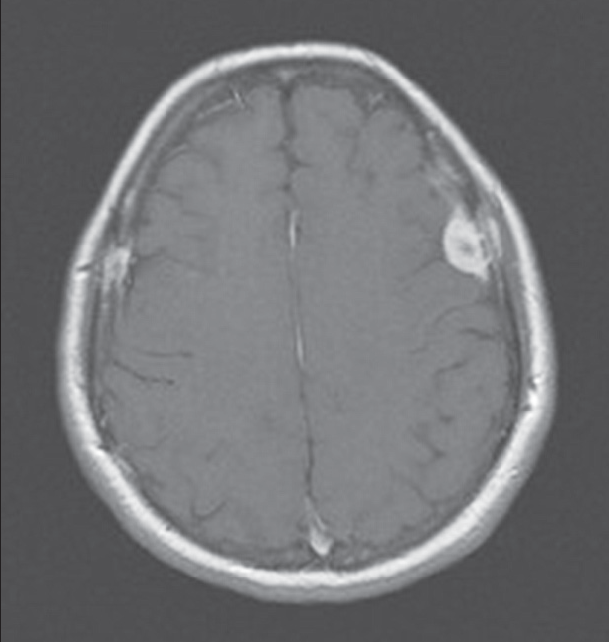

Teaching Neuroimages Numb Chin Syndrome In A Patient With Breast Cancer Neurology